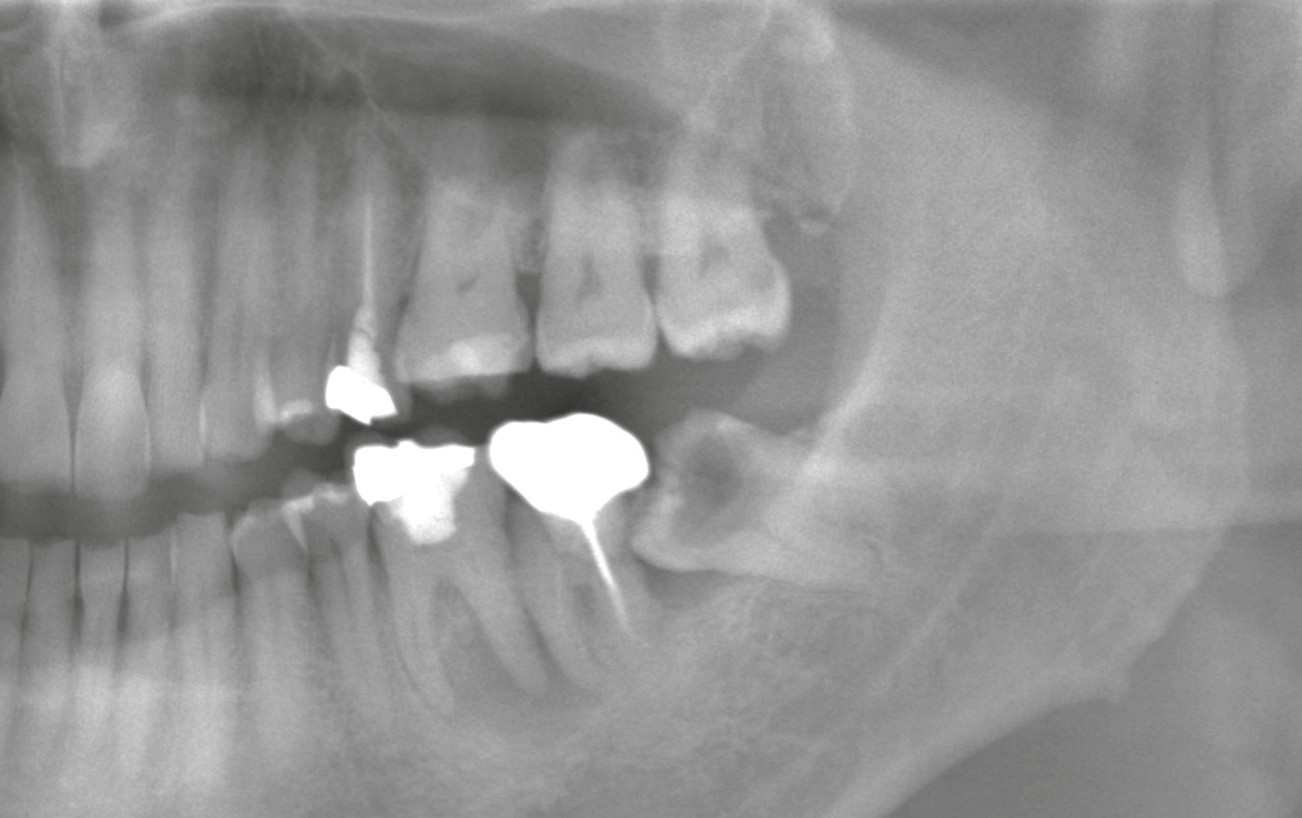

■ レントゲンで確認された所見

レントゲン撮影の結果、

左下の親知らずは深い虫歯が神経にまで達しており、感染が深部に及んでいました。

このようなケースでは、痛みが非常に強く出やすく、また鎮痛薬も効きにくくなる傾向があります。

■ 治療方針と抜歯の判断

虫歯が歯根まで進行し、かつやや水平に傾いて生えているため、

補綴(被せ物)での保存は困難と判断。

また、対合する上の親知らずも機能しておらず、同様に虫歯に罹患していたため、

上下同時に抜歯を実施しました。